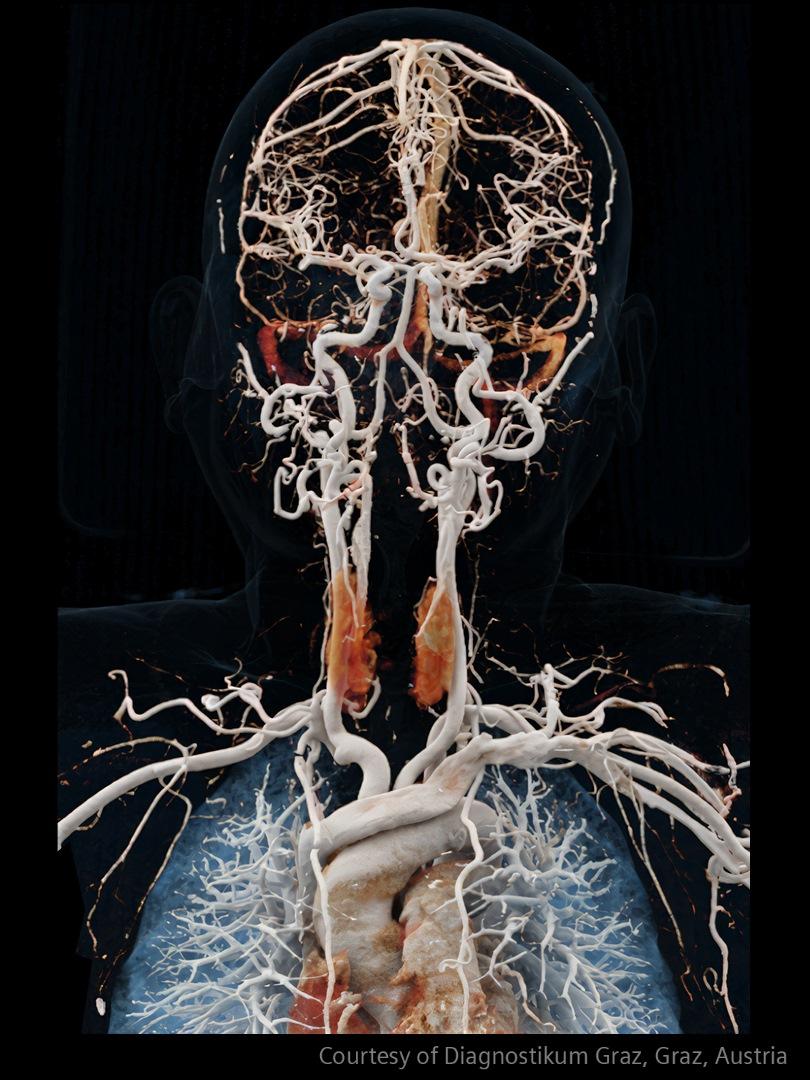

Im Bereich der Schlaganfallversorgung zählt jede Sekunde . Schnelle und präzise Bildgebung ist entscheidend, um das Ausmaß der Hirnschädigung zu beurteilen und die sofortige Behandlung einzusteuern. Angiographie, MRT, CT, Labordiagnostik und Ultraschall sind unverzichtbare Werkzeuge, um Schlaganfalltyp, -bereich und -schwere zu bestimmen. Durch technologische Fortschritte in der Bildgebung sind heute noch schnellere Aufnahmen, eine bessere Auflösung und eine optimierte Darstellung von Gehirnstrukturen und Blutgefäßen möglich. Innovationen wie Perfusionsbildgebung, Echtzeit-Gefäßkartierung und KI-gestützte Diagnostik revolutionieren die Abläufe bei Schlaganfällen und ermöglichen präzise zeitnahe Interventionen.